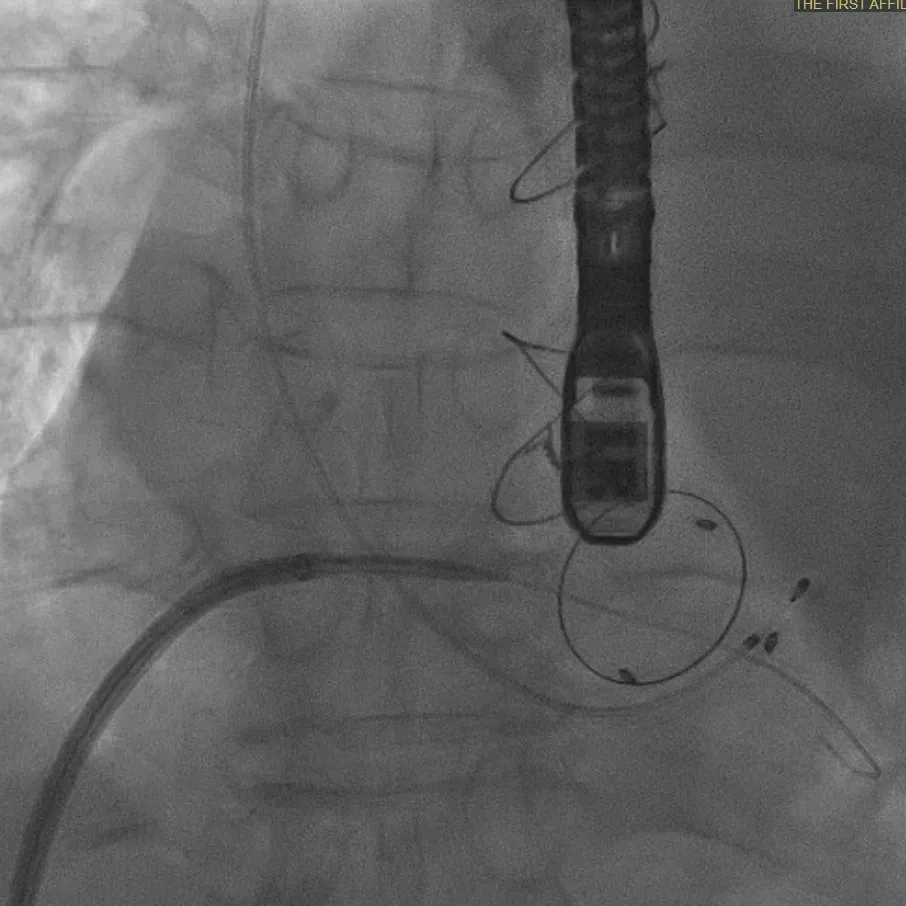

▲穿刺房间隔